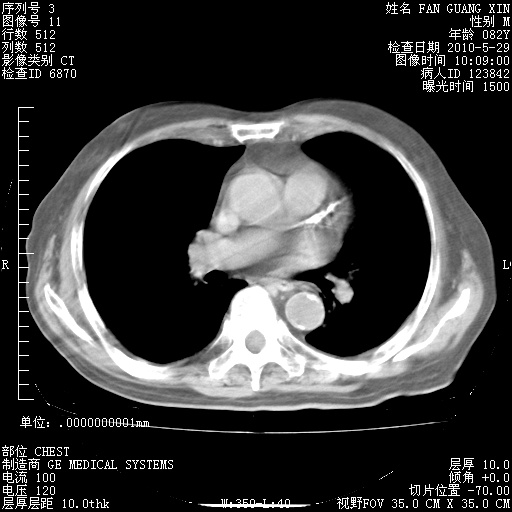

治疗3周后的肺部CT纵隔窗

再治疗10天后的肺部CT 纵膈窗

阅读此次胸部CT,肺间质渗出性改变较入院时有吸收。目前从体温、白细胞、中性分叶明显增高,肯定存在细菌感染(发生医院感染哦,若无消化道及泌尿系统等感染的依据,肺部感染可能大)。若你院头孢哌酮舒巴坦钠耐药率较高,同意你的方案,若48小时体温仍高,可考虑使用碳青霉稀类抗菌药物,同时可予超声雾化、注意滴数时加大液体量。白蛋白33.30g/L较低哦,需加强营养等支持治疗。